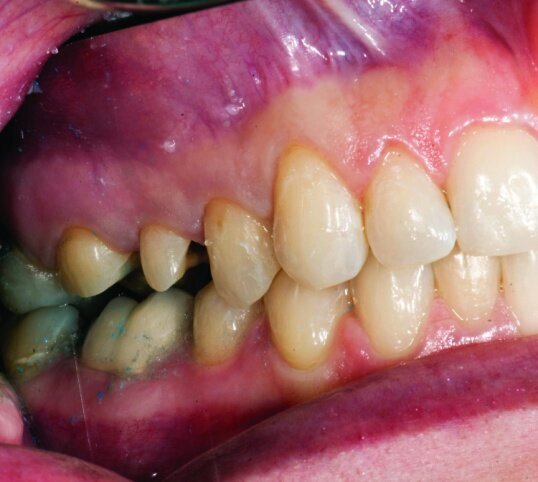

The final result was minimally invasive restorations that appear and function naturally, while decreasing risk of tooth fracture, and minimize further risk to the teeth. (Figs. 35a–36b).